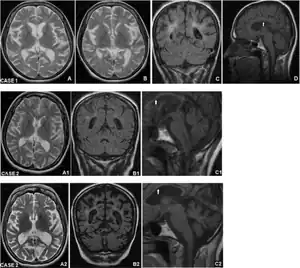

| Brain MRI imaging Kufs disease type B- a and b) Axial T2-TSE ,c) coronal T2-FLAIR d), and sagittal T1-TSE sections at onset of cognitive impairment showing cortico-subcortical atrophy, a1)displayed brain atrophy axial T2-TSE b1), coronal T2-FLAIR c1) and sagittal T1-TSE a2)axial T2-TSE,b2) coronal T2-FLAIR c2) sagittal T1-TSE scans 9 years later | |